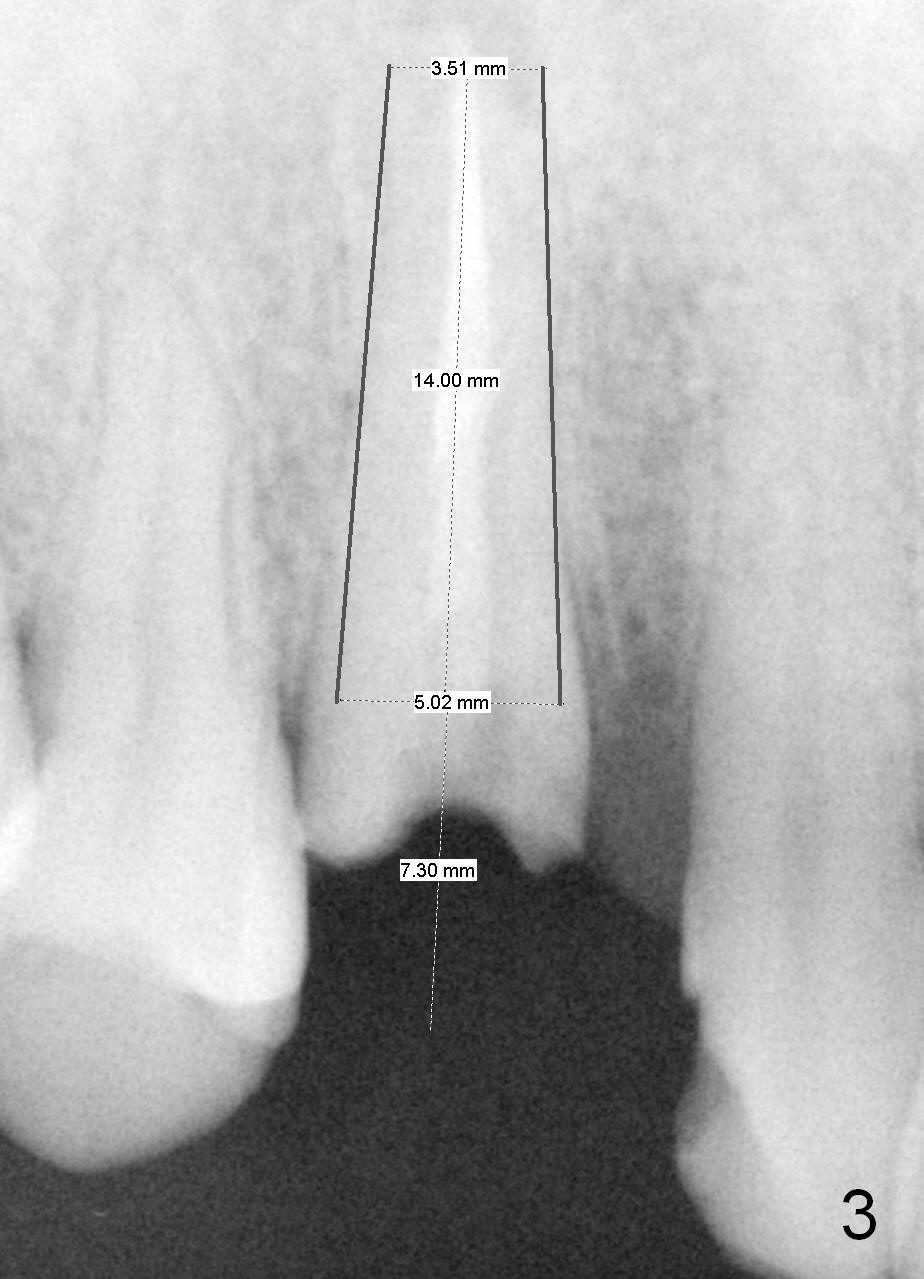

Recently tissue-level implants have been used successfully for upper canines (1 , 2). The prominent feature of the implants is the length (20 mm) with primary stability. Although the longest bone-level implant is 14 mm, the advantage of the latter is its temporary abutment. With it, the tissue forms beautifully with a central incisor. A 43-year-old man fractures #6 (Fig.1: red dashed line: nasal floor). Although a 5x20 mm tissue-level implant is a good option (Fig.2), a 5x14 mm bone-level implant should be able to achieve primary stability (Fig.3). Anyway, either implant should be placed as palatal as possible, particularly for bone-level one, because the temporary abutment should exit palatal to the incisal edge. If position or angulation of the bone-level implant is not ideal, an angled abutment will be used. Check occlusion carefully before and after immediate provisional cementation. Is the 5x14 mm implant long enough?